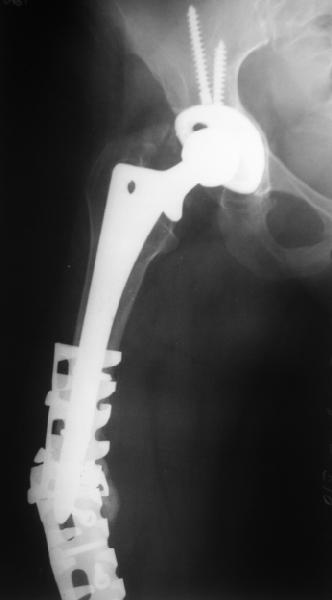

Female, rheumatoid, THA in 2003, car accident in 2006, failed plating. Nailing in Oct 2007. The nail is solid with hollow proximal part where the stem is docked. Last images are in 1 year after

nailing.

I have refreshed respect for the mighty femur and it’s incredible/remarkable ability to unite, regardless of what we do to it.

The femur responded by failure to Mennen plating (DePuy Bridge plate). So i would add that the ability to unite is realized in mechanically and biologically sound conditions.